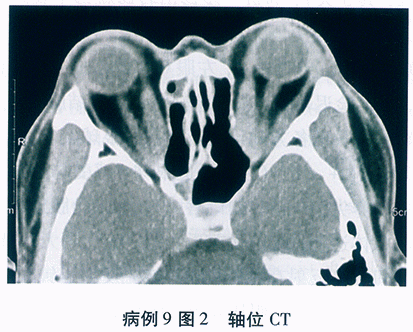

角膜地形图: 图9-3.

角膜地形图: 高度散光,角膜屈光力>48D

基于以上病史、眼部表现及辅助检查结果分析:双眼圆锥角膜(右眼急性圆锥)诊断明确。